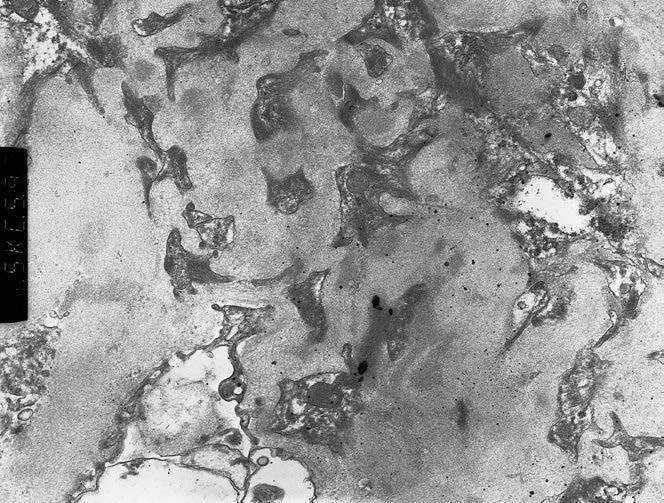

A 77-year-old man with chronic kidney disease due to hypertension, presented with hematuria, nausea, and vomiting and red discoloration of urine. Laboratory data Table 1, serology tests Table 2. Renal ultrasonography unremarkable. Patient developed hemoptysis. Chest radiograph revealed bilateral diffuse airspace opacities. Intravenous methylprednisolone was administered. The patient received hemodialysis. Renal biopsy showed mesangial hypercellularity (Figure 1), crescents (Figure 2), segmental necrosis (Figure 1). There was moderate tubular atrophy an occasional eosinophil. Immunofluorescence microscopy demonstrated granular IgG (1+), C3 (2+), and C1q (1+) deposition in the mesangial areas and glomerular basement membranes (Figure 3). EM showed numerous electron-dense deposits in the mesangial areas and few subepithelial and subendothelial electron-dense deposits (Figure 4). Focal effacement of podocyte foot processes was noted. Histological diagnosis: immune complex-mediated necrotizing and crescentic glomerulonephritis.

Figure 4. EM: electron dense immune complex deposits in glomerular mesangium (high power)